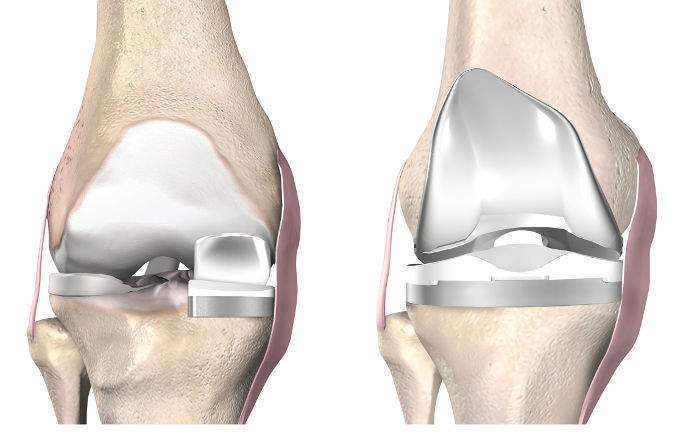

εικ. Αριστερά: Γόνατο με Μονοδιαμερισματική Αρθροπλαστική. Δεξιά γόνατο με Ολική Αρθροπλαστική